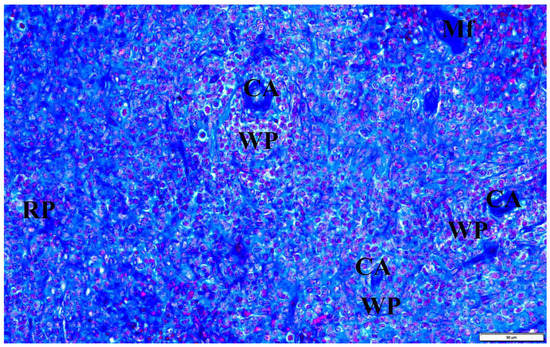

In the presented studies, in the histological structure of the spleen of intrauterine infected rats with B. microti, no clear deviations from the normal architecture of the organ were observed, appropriate to the young age of the observed individuals. Both white and red pulp were visible. However, the line between them was blurred (Figure 8). The lymphoid follicles were irregular in shape and the marginal layer was barely perceptible. The fibrous capsule of the spleen of rats under physiological conditions is characterized by a small amount of connective tissue. In the observed preparations of spleen sections taken from rats with congenital babesiosis, a small amount of it was visible with the presence of mesothelial cells covering its surface. The connective tissue capsule detached from the parenchyma of the organ in places, creating fissured spaces. These dissections indicate degenerative changes, possibly associated with edema. The trabeculae extending from the splenic capsule were visible and contained vessels with fibrin-precipitated hyperemia and numerous blood cells adhering to the endothelial wall (Figure 9). In addition, a characteristic feature was the differentiation of erythrocytes.

Figure 8.

The spleen of a rat with transplacental infection with B. microti 3 weeks after birth. CA—central artery, Mf—macrophage, WP—lymphoid follicles (white pulp), RP—red pulp.